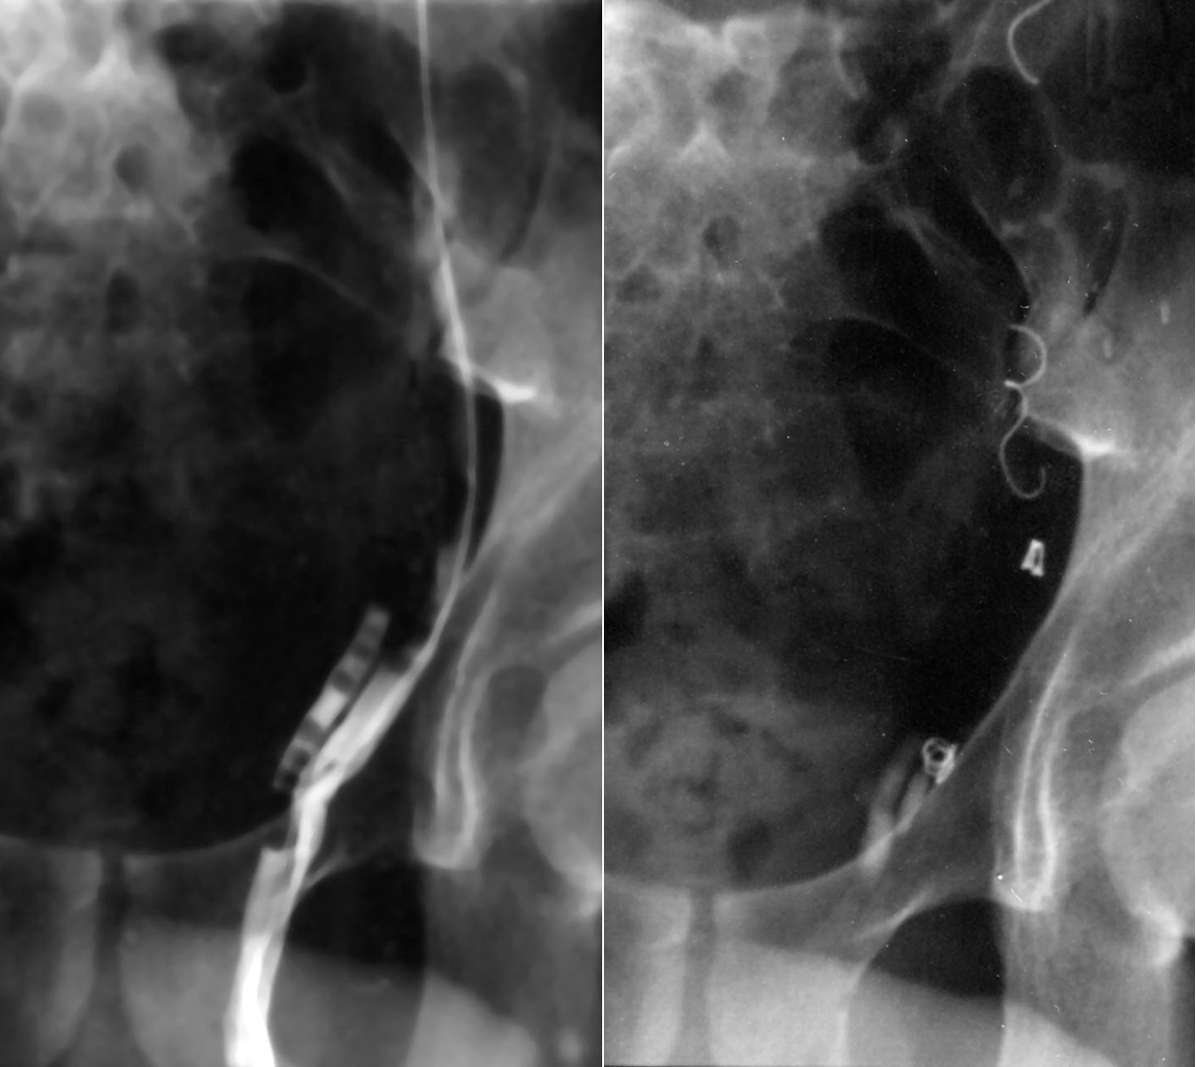

Venography & venous occlusion, using plugging materials such as foam, coils & sponges, is often employed to treat varicoceles (see image below) and avoids the need for surgery with all its attendant risks. The complication rate is low and the procedure is both safe & effective in relieving symptoms, although probably not quite as effective as surgery.

Before (L) & after (R) coil & sponge occlusion of a varicocele

(via a puncture of the right femoral vein)